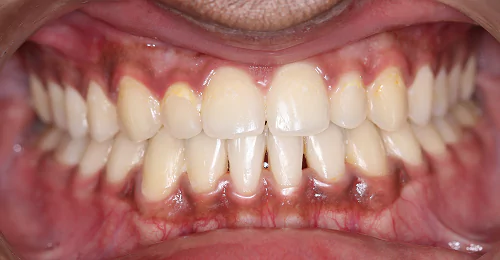

Orthodontic Case – III

(Case Done by Dr. Sonali Deshmukh M.D.S. / Orthodontist )

Deep – II Correction

Pre Treatment